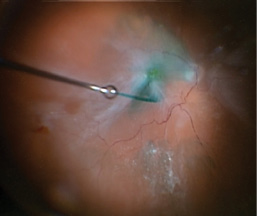

I turned my attention to the posterior pole. Indocyanine green (ICG) was used to stain the ILM (Figure 3), which was gently peeled using the MaxGrip forceps (Figure 4). This was followed by an air-fluid exchange using a soft-tip cannula (MedOne Surgical) taking care to remove all of the subretinal fluid through the draining retinotomy. The retina flattened nicely. Silicone oil (Silikon 1000, Alcon) was infused through the 25-gauge cannula for longer-term tamponade.

Figure 3. Intraoperative image showing the use of ICG to stain the ILM. Note the stretch hole in the periphery.